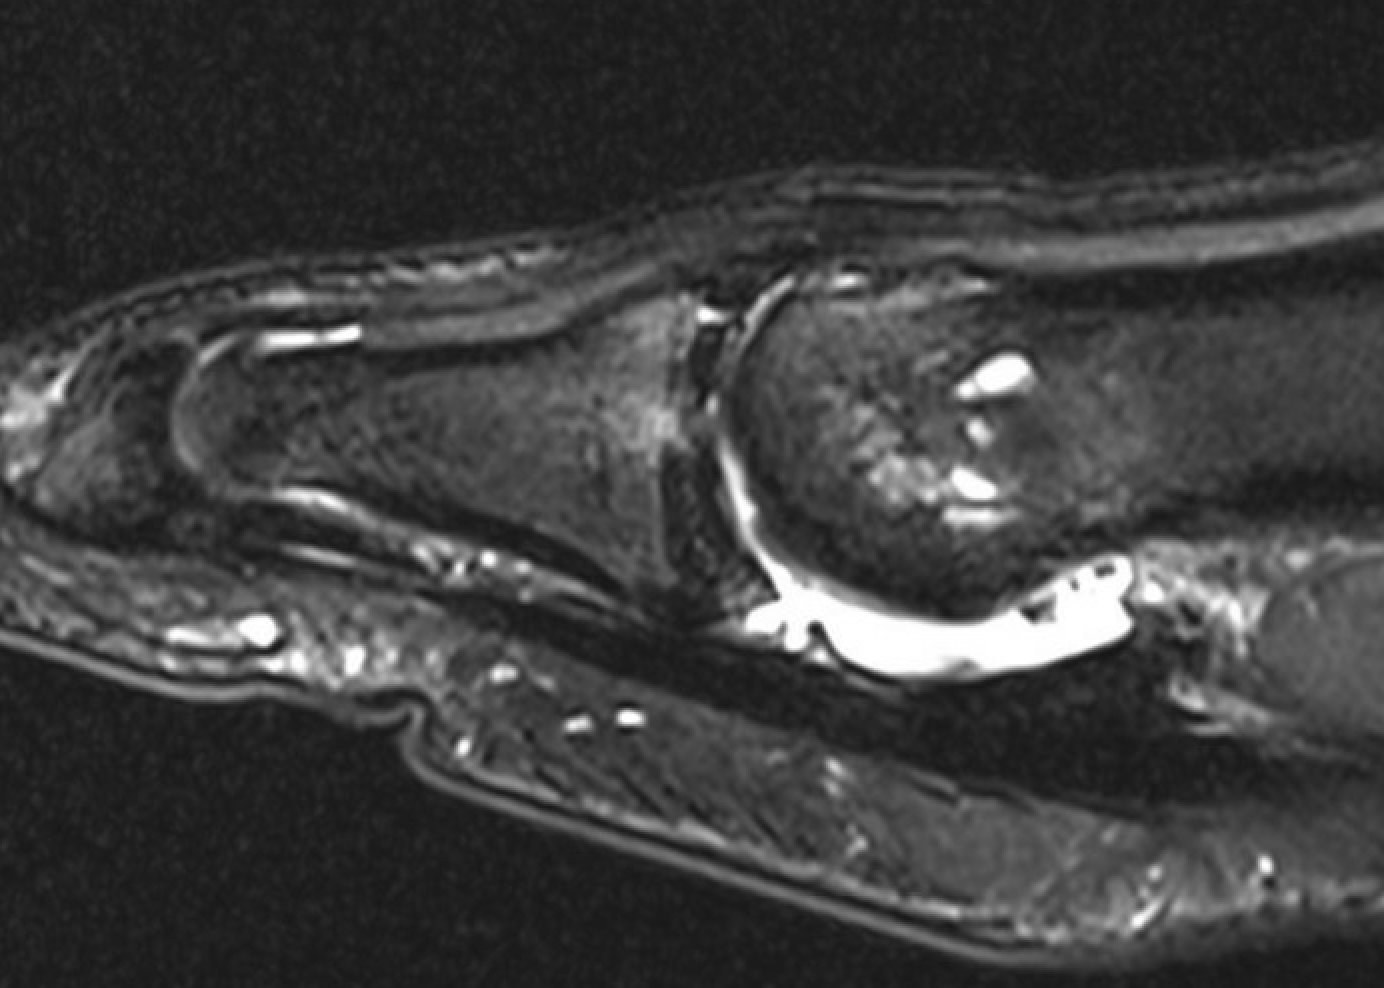

MRI

Sagittal images

Complete plantar plate avulsion